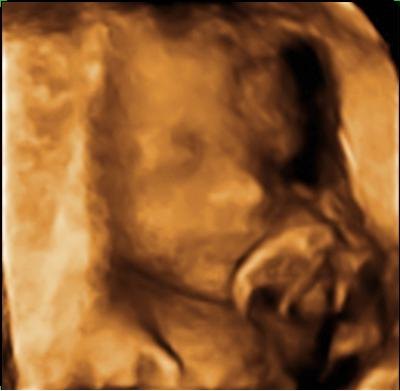

Ser frem til at læse om din scanning